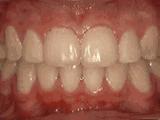

第七种:

牙列稀疏,牙槽骨过长,或者牙齿少,导致排列太宽松,零零散散,经过矫正后的是这样的~